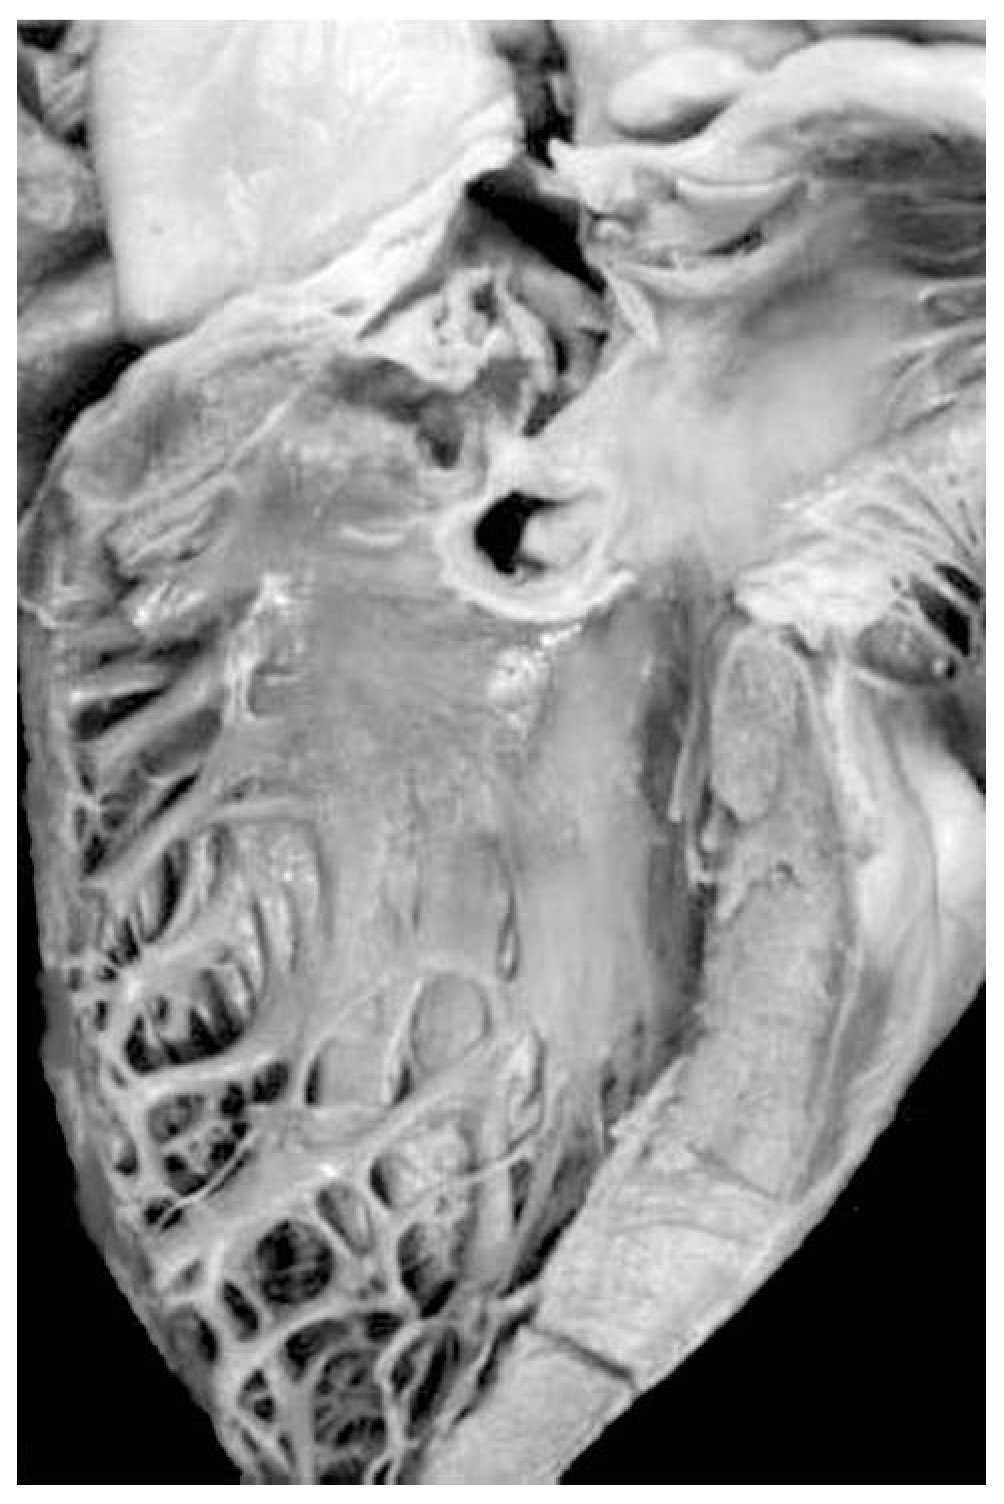

Atrio-ventricular connection: Ventricles are recognized by the trabecular septum's anatomic features. The right ventricle (Figure 3) has a trabecular septum with very thick muscular bands and it also has a structure, the moderator band, inserted in the interventricular septum and in the free wall of the right ventricle, whereas the left ventricle has a trabecular septum with very thin muscular bands in the apical section and it is smooth in the upper section (Figure 4). The former has a group of papillary muscles inserted in the free wall, and the latter has two groups of papillary muscles which are also inserted in the free ventricular wall. Trabecules provide a cavernous-type inner morphological appearance to the right ventricle, whereas the left ventricle has an areolar appearance.

Figure 3. Internal morphology of the right ventricle.